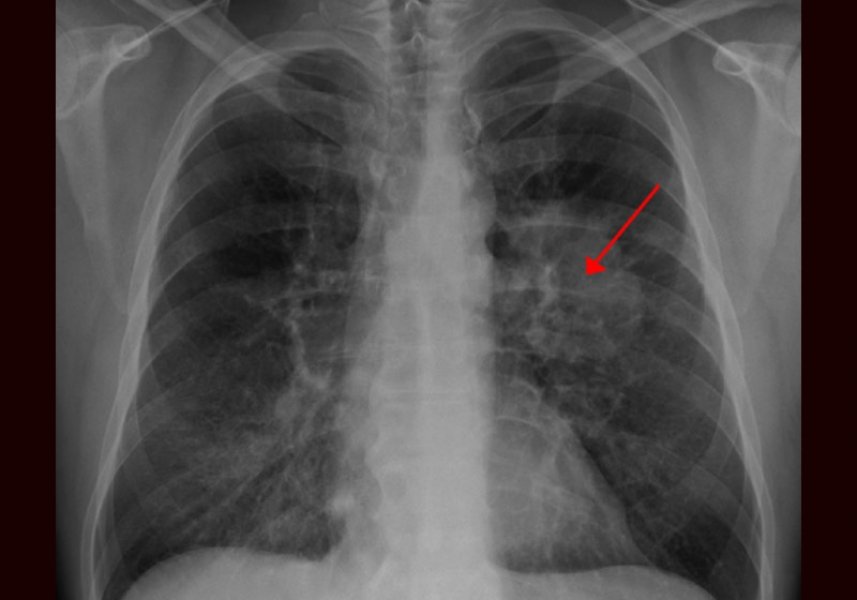

O procedimento cirúrgico foi feito com sucesso no Hospital Beilinson e “pode mudar a maneira” como os cânceres são tratados ultimamente. O paciente, que não teve o nome revelado, tem aproximadamente 40 anos. Ele foi hospitalizado após um tumor no pulmão esquerdo bloquear a artéria principal, levando ao colapso.

No Centro Médico Rabin, em Petah Tikva, os médicos perceberam que o pulmão ficaria ressecado até que surgisse um doador para um possível transplante. “Se tivéssemos simplesmente cortado o pulmão, aguardando um transplante, o paciente continuaria com risco de vida”, disse Yuri Faischowitz, diretor da Unidade de Cirurgia Cardiotorácica de Beilinson, ao Dr. Itai Gal, da Ynet News. .

Durante a cirurgia, no mês passado, o homem continuou a respirar pelo pulmão bom, enquanto o outro era desconectado, limpo do tumor e reconectado – após inflá-lo para garantir que continuasse funcionando e que o tecido estava saudável.